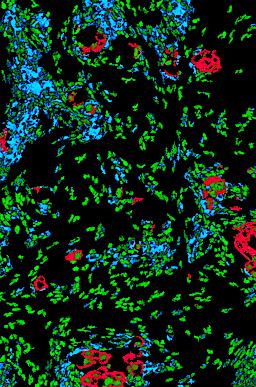

Pancreatic ductal adenocarcinoma is a lethal disease with limited treatment options and poor survival. We studied 83 spatial samples from 31 patients (11 treatment-naïve and 20 treated) using single-cell/nucleus RNA sequencing, bulk-proteogenomics, spatial transcriptomics and cellular imaging. Subpopulations of tumor cells exhibited signatures of proliferation, KRAS signaling, cell stress and epithelial-to-mesenchymal transition. Mapping mutations and copy number events distinguished tumor populations from normal and transitional cells, including acinar-to-ductal metaplasia and pancreatic intraepithelial neoplasia. Pathology-assisted deconvolution of spatial transcriptomic data identified tumor and transitional subpopulations with distinct histological features. We showed coordinated expression of TIGIT in exhausted and regulatory T cells and Nectin in tumor cells. Chemo-resistant samples contain a threefold enrichment of inflammatory cancer-associated fibroblasts that upregulate metallothioneins. Our study reveals a deeper understanding of the intricate substructure of pancreatic ductal adenocarcinoma tumors that could help improve therapy for patients with this disease.